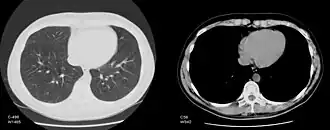

Изменение окна изображения

Обычный компьютерный монитор способен отображать до 256 оттенков серого цвета, некоторые специализированные медицинские аппараты способны показывать до 1024 оттенков. В связи со значительной шириной шкалы Хаунсфилда и неспособностью существующих мониторов отразить весь её диапазон в чёрно-белом спектре, используется программный перерасчёт серого градиента в зависимости от выбранного интервала шкалы. Чёрно-белый спектр изображения можно применять как в широком диапазоне («окне») денситометрических показателей (визуализируются структуры всех плотностей, однако невозможно различить структуры, близкие по плотности), так и в более-менее узком с заданным уровнем его центра и ширины («лёгочное окно», «мягкотканное окно» и т. д.; в этом случае теряется информация о структурах, плотность которых выходит за пределы диапазона, однако хорошо различимы структуры, близкие по плотности). Изменение центра окна и его ширины можно сравнить с изменением яркости и контрастности изображения соответственно.